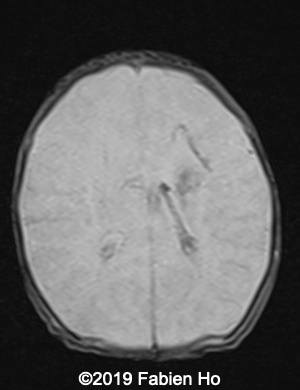

Images 4-11, fetal brain MRI at 28 weeks: the left frontal lesion hence shows DWI hyperintensity, with T2* and T1 peripheral hyperintensity: ischemia with peripheral subacute hemorrhage. Note also that there is an associated blood clot in the left lateral ventricle. There is no obvious mass effect, nor peripheral edema. All these findin>gs are very suggestive of a clastic lesion.

Axial T2w

4

5